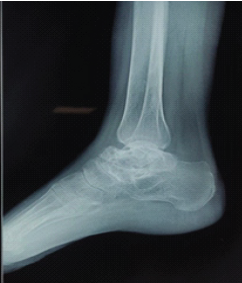

Aneurysmal Bone Cyst of Talus: Case Report of a Rare Presentation

Sohail Ahmad , Faisal Harun , Adnan Anwar , Mohd Owais Ansari , Syed Mohd Shoaib , Syed Fahad Shaan